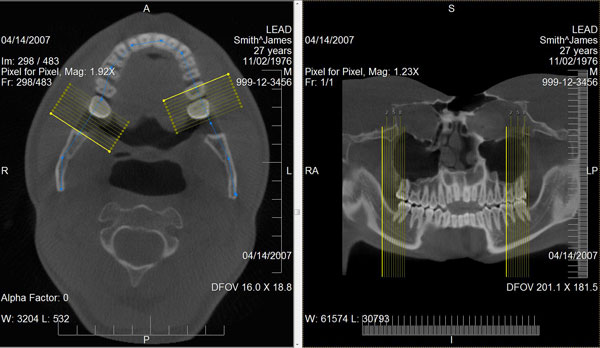

曲面多平面重组

通过使用先进的视角分析算法将弯曲的部分投影到一个平面上,曲面多平面重组可从一堆二维切片中生成二维的全景影像和近轴切影像。曲面多平面重组的使用在牙科和断层扫描(ct)专家中非常流行,他们需定期检查具有弯曲几何的骨骼,如牙齿和血管。

曲面多平面重组功能:

• 添加、删除和移动曲线上的全景点

• 可从每一段曲线中创建一个或多个近轴的切割

• 诸多属性可轻松控制曲线的信息、曲线上的点、近轴的距离、近轴线的长度、颜色等等

• 导出并保存生成的影像

leadtools medical image viewer控件支持曲面多平面重组功能,允许开发者将此功能无缝的添加到他们的应用程序中。medical viewer控件提供了交互式的工具,可以绘制曲线、移动全景点、生成全景影像、自动创建近轴线和生成近轴影像。结果影像可和影像分析工具一起使用,如window/level,alpha,平移、缩放、滚动和测量。它还提供了影像处理和标注的工具。

curved mpr / panoramic screenshot